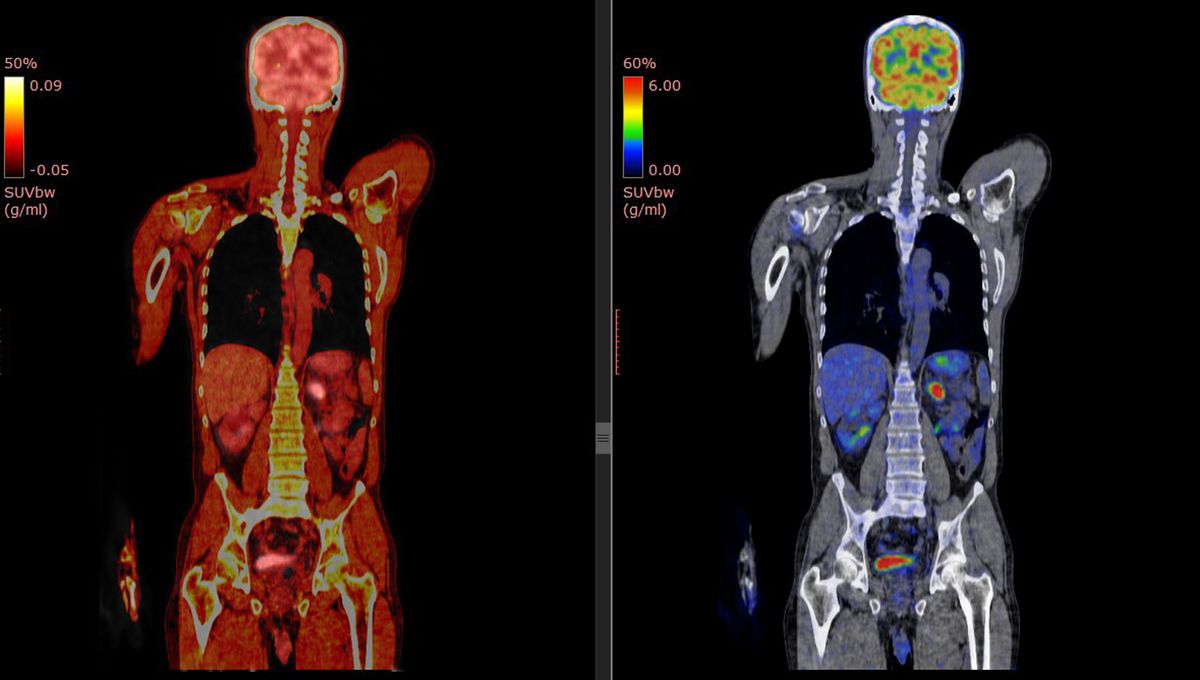

A new study using PET scans has found that autistic individuals have fewer synapses in their brains, which correlates with more pronounced autism traits such as social and communication difficulties. This discovery marks the first time synaptic density has been measured in living autistic individuals and could revolutionize diagnostic and treatment approaches, potentially leading to more targeted interventions. The research highlights the importance of understanding the biological underpinnings of autism to improve support and quality of life for those on the spectrum.